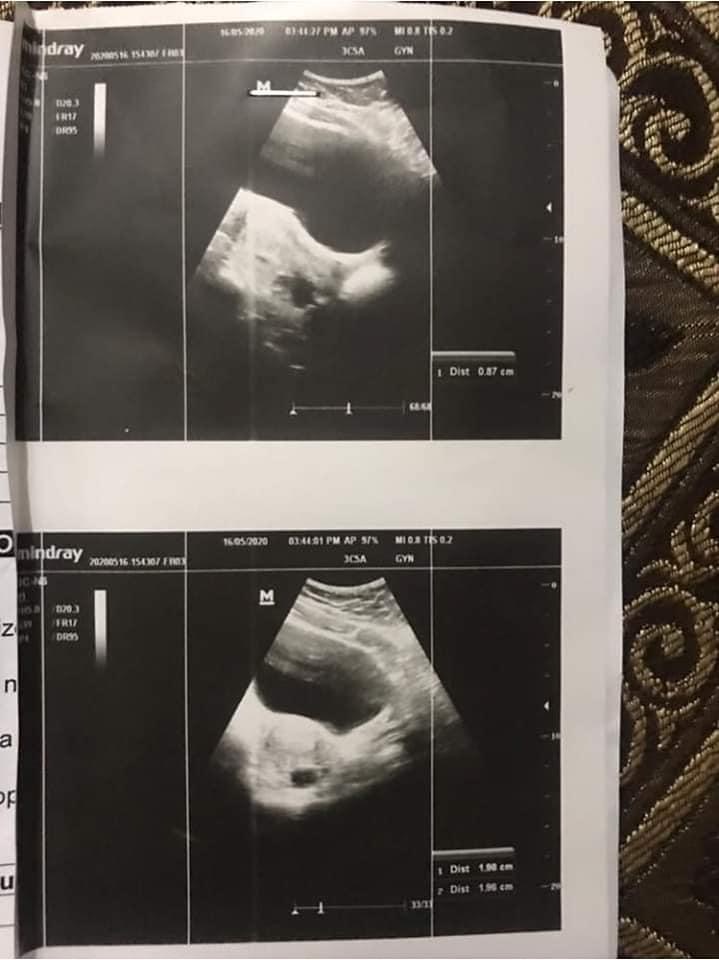

Please post this anonymous,, Mjhy pcos dignose hwa tha,.shadi ko 2 saal hogay hain pehly hmny try ni kia baby k lye,.ab 4 5 mah sy try kar rhy thy lekin ni hwa concieve tou doc ny 22 march ko clomid 50 mg ka cycle dya,.usky bad mai ny due date k bad chek kia tou pregnency ni thi phr 8th april sy mjhy bleeding start hogai kabhi kam kabi zada jo abi tk horai hy,.17 may ko mai ny transamine 500 mg subha sham 5 days khai lekin stop ni hwi bleeding,.ab doc ny kaha hy k Just-n 5mg 21 days khao,,16 may ko may bny scan b karwaya tha usmain sb thek aya hy,.pehly both ovries cystic thi ab koi cyst ni hy,.ab mai kia karo just N start kardo kia?